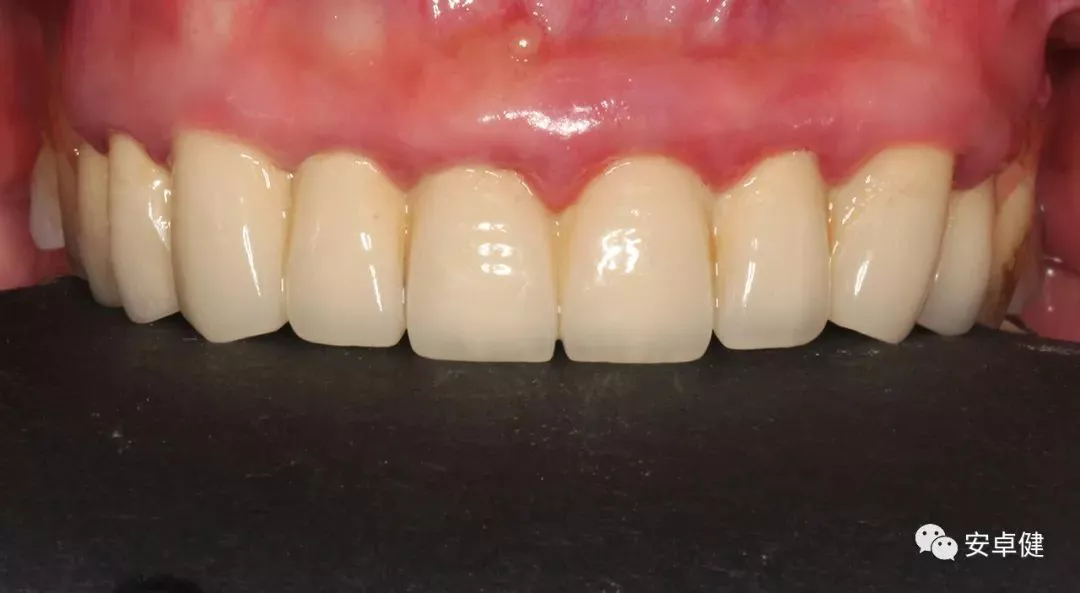

• 完成最终修复体制作。

最终修复体合面照

最终修复体正面照

最终修复体正面咬合照

最终修复体侧面咬合照